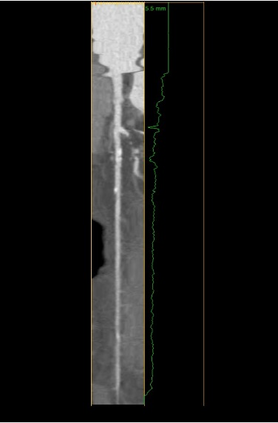

The standard non-invasive imaging technique used to assess the severity and extent of Coronary Artery Disease (CAD) is Coronary Computed Tomography Angiography (CCTA). However, manual grading of each patient's CCTA according to the CAD-Reporting and Data System (CAD-RADS) scoring is time-consuming and operator-dependent, especially in borderline cases. This work proposes a fully automated, and visually explainable, deep learning pipeline to be used as a decision support system for the CAD screening procedure. The pipeline performs two classification tasks: firstly, identifying patients who require further clinical investigations and secondly, classifying patients into subgroups based on the degree of stenosis, according to commonly used CAD-RADS thresholds. The pipeline pre-processes multiplanar projections of the coronary arteries, extracted from the original CCTAs, and classifies them using a fine-tuned Multi-Axis Vision Transformer architecture. With the aim of emulating the current clinical practice, the model is trained to assign a per-patient score by stacking the bi-dimensional longitudinal cross-sections of the three main coronary arteries along channel dimension. Furthermore, it generates visually interpretable maps to assess the reliability of the predictions. When run on a database of 1873 three-channel images of 253 patients collected at the Monzino Cardiology Center in Milan, the pipeline obtained an AUC of 0.87 and 0.93 for the two classification tasks, respectively. According to our knowledge, this is the first model trained to assign CAD-RADS scores learning solely from patient scores and not requiring finer imaging annotation steps that are not part of the clinical routine.